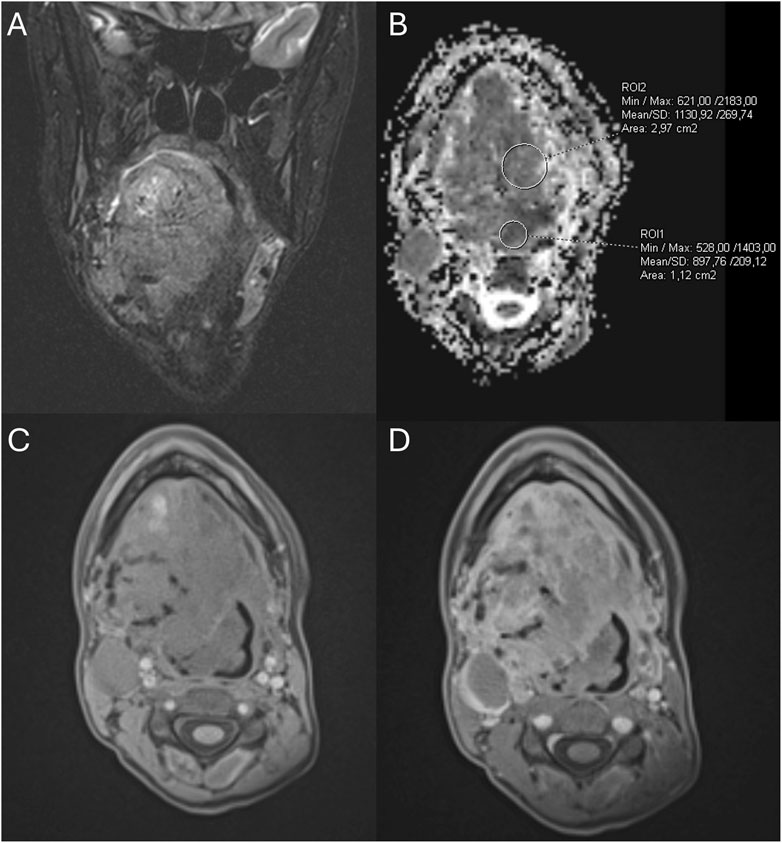

ABSTRACT Introduction Vascular anomalies (VAs), comprising vascular tumors and malformations, are commonly diagnosed based solely on clinical evaluation and imaging. Soft tissue sarcomas (STS) may mimic VAs clinically and radiologically, leading to misdiagnosis, delayed treatment, and suboptimal outcomes. This systematic review aimed to summarize patients with a pathological diagnosis of STS who were initially misdiagnosed with benign VAs, highlighting diagnostic pitfalls. Materials & Methods This systematic review (PROSPERO ID: CRD42024615285) followed PRISMA 2020 guidelines. Inclusion criteria were patients with histologically confirmed STS, initially misdiagnosed as benign VAs based on clinical and/or radiological features. Literature from five databases was reviewed without language or date restrictions. One additional case of alveolar soft part sarcoma initially misdiagnosed and mistreated as an arteriovenous malformation from the authors' institution was added to the analysis. Results The systematic search yielded a total of 96 patients with STS initially misdiagnosed as benign VAs (95 from 77 publications, one own case). Median age at presentation was 6 months (range: newborn–88 years). The most frequent symptom was a swelling or a mass (75%). In most cases, the misdiagnosis was both clinical and radiological. Median diagnostic delay was 5.5 months. Fifty-nine (61.5%) patients received treatment for the misdiagnosed benign VA, including local interventions (51.0%) and systemic therapies (17.7%). The most commonly misdiagnosed STS subtypes were infantile fibrosarcoma, alveolar soft part sarcoma, rhabdomyosarcoma, dermatofibrosarcoma protuberans, angiosarcoma, and Ewing sarcoma. Conclusions Several STS subtypes may mimic benign VAs clinically and radiologically. Misuse of outdated terminology and limited awareness among clinicians contribute to diagnostic delays. To avoid misdiagnoses, the care for patients with benign VAs should be provided by specialists familiar with the classification and natural history of these lesions. In patients diagnosed with benign VAs based on clinical and/or imaging features only, all findings should clearly support the diagnosis. Any ambiguity warrants prompt referral to a tertiary center. A biopsy should be considered in doubtful or atypical cases.